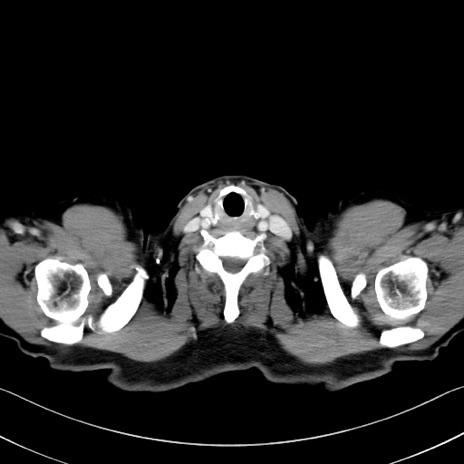

冠状断像